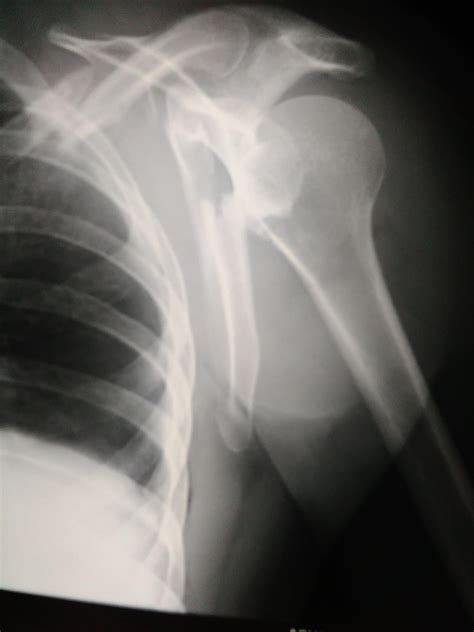

• Imaging Tests: X-rays are the primary imaging tool used to diagnose a fractured shoulder blade. They can show the location and extent of the fracture. In some cases, additional imaging tests such as CT scans or MRIs may be ordered to provide more detailed information.

• Deformity: In some cases, there may be a visible deformity or a bump on the shoulder.